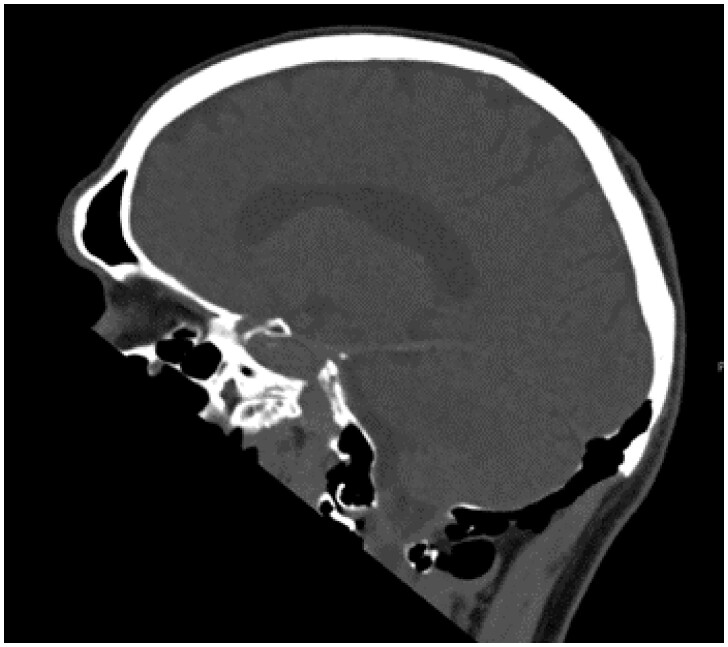

Hyperpneumatization is a rare pathological process where air-filled cavitation form within solid bone architecture occurring at sites where physiological pneumatization is not seen. Extension of this process into the atlanto-occipital region is considered extremely rare and is only quoted several times in the literature. In this case report, we present a 66-year-old man who presented with an 8-month history of a worsening frontal headache and blocked sensation in his left ear. Subsequent CT head evaluation revealed hyperpneumatization affecting C1 vertebra, temporal and occipital bones with extension into the clivus. A rare complication of epidural emphysema was seen. The aetiology of hyperpneumatization is uncertain, although it is thought to be either congenital or acquired. In our case, clinical suggestion of eustachian tube dysfunction and radiological findings of thickened sinus mucosa and a unilateral nasal polyp point to chronic recurrent coryzal illnesses, which may indicate an acquired mechanism. Management is mostly conservative with surgical management reserved for high risk or refractory cases.